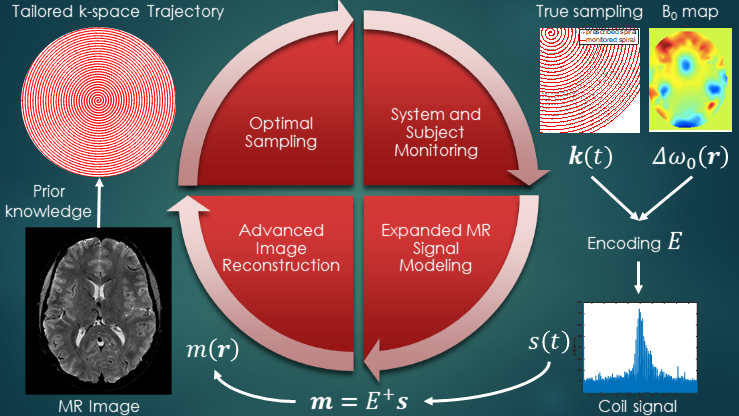

Magnetic resonance imaging (MRI) offers a unique opportunity to non-invasively study the human brain, equipped with a wealth of contrasts (to disentangle structures and functions), and a favourable window of spatiotemporal resolution. But to expand its clinical and neuroscientific scope, MRI has to become faster and more robust. A key ingredient to this end is a mechanistic understanding of the imaging physics, and its consideration in the way we acquire and reconstruct MR images. This comprises the choice of optimal sequence and sampling strategy for the target application (e.g., spiral trajectories for short echo-time) a detailed characterization of both hardware imperfections (e.g., heating/field drift and trajectory errors) and subject-related noise sources (e.g., breathing, motion) giving rise to image artifacts, the accurate inclusion of this information into an expanded signal model of the MR imaging process and advanced image reconstruction techniques capable of inverting these intricate models. This integrated approach leads to better imaging data tailored to the analysis and diagnostic purpose of the MR exams. The characterization of each scan’s imaging peculiarities allows for better comparability of multi-site studies in the era of big data. At the other end of the spectrum, personalized medicine requires individualized MR imaging protocols that are enabled by flexible and extendable signal models and reconstructions.